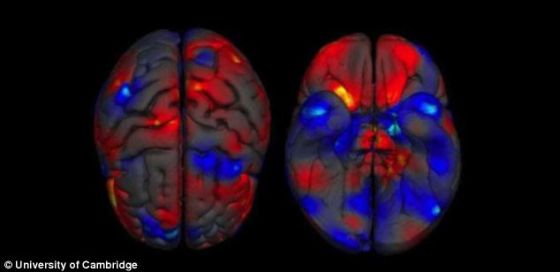

照片展示了这个大脑上面和下面的构造,揭示了灰质容积的差异。红色代表女人大脑较大容积区域,蓝色代表男人大脑较大容积区域。

科学家发现,男人大脑总量平均比女人的大8%到13%。平均来说,在颅内腔、全脑、大脑、端脑、灰质、白质、充满脑脊液的区域和小脑等方面,男人比女人还有更大的绝对容积。随着研究深入,科学家发现男人和女人大脑几个区域的容积存在差异,这些区域包括处理情感的边缘系统和语言系统等。